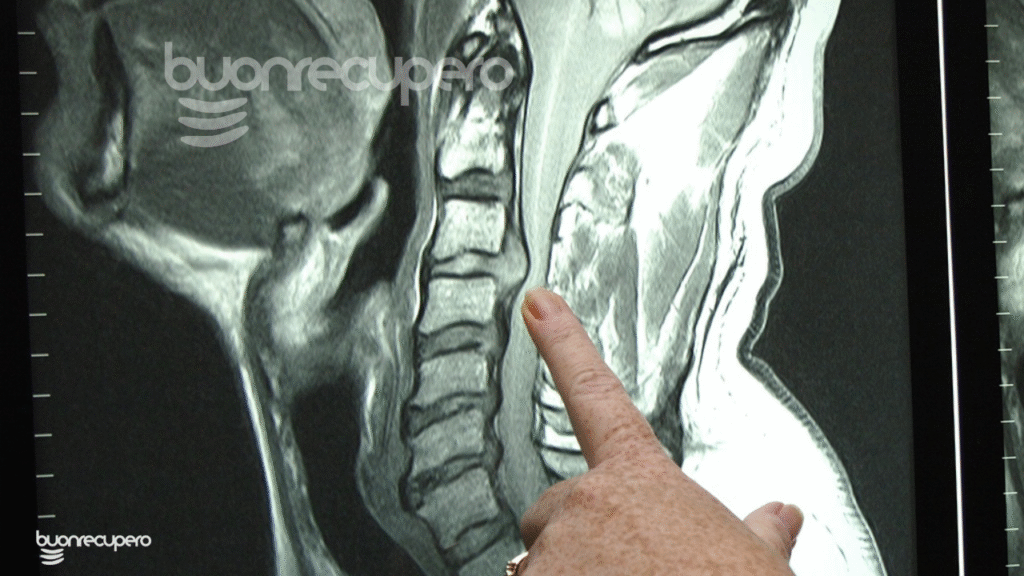

Cos’è l’ernia cervicale (spiegata senza confusione)

L’ernia cervicale è una condizione in cui il disco intervertebrale del tratto cervicale perde la sua normale posizione o integrità, andando a irritare o comprimere una radice nervosa.

Serve davvero la risonanza magnetica?

molte persone hanno ernie cervicali asintomatiche

il dolore non correla sempre con ciò che si vede alla risonanza